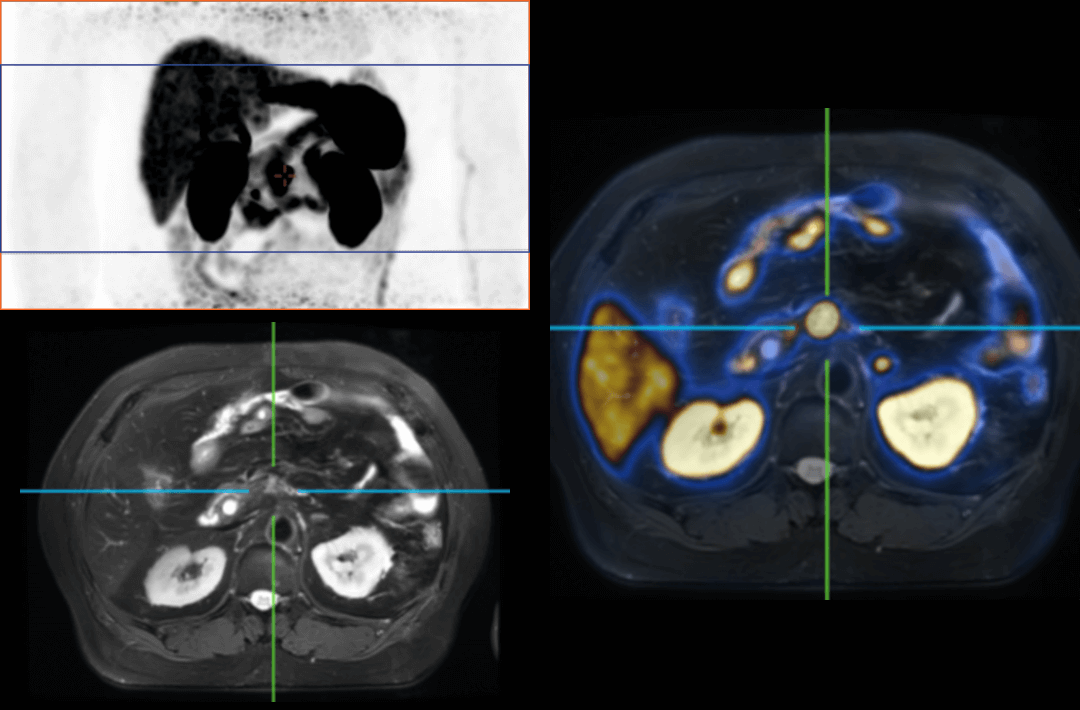

The following are the cases of optimized TNM staging of breast cancer, esophageal cancer, prostate cancer and other diseases under the long axial field of "spatio-temporal integration" ULTRA-clear TOF PET/MR. Thanks to Capital Medical University Xuanwu Medical Treatment for providing the image.